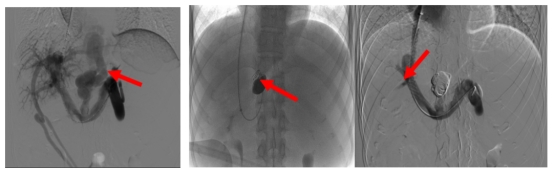

2025-10-22五院技术 | 94岁老奶奶“腿梗”, 心脏专家妙手“通脉”

时至金秋,天气转凉,昼夜温差加大,平时稳步健行的94岁周奶奶(化名)近1个月出现间歇性左下肢疼痛,步行时步履蹒跚如“跛行”,生活质量骤降。